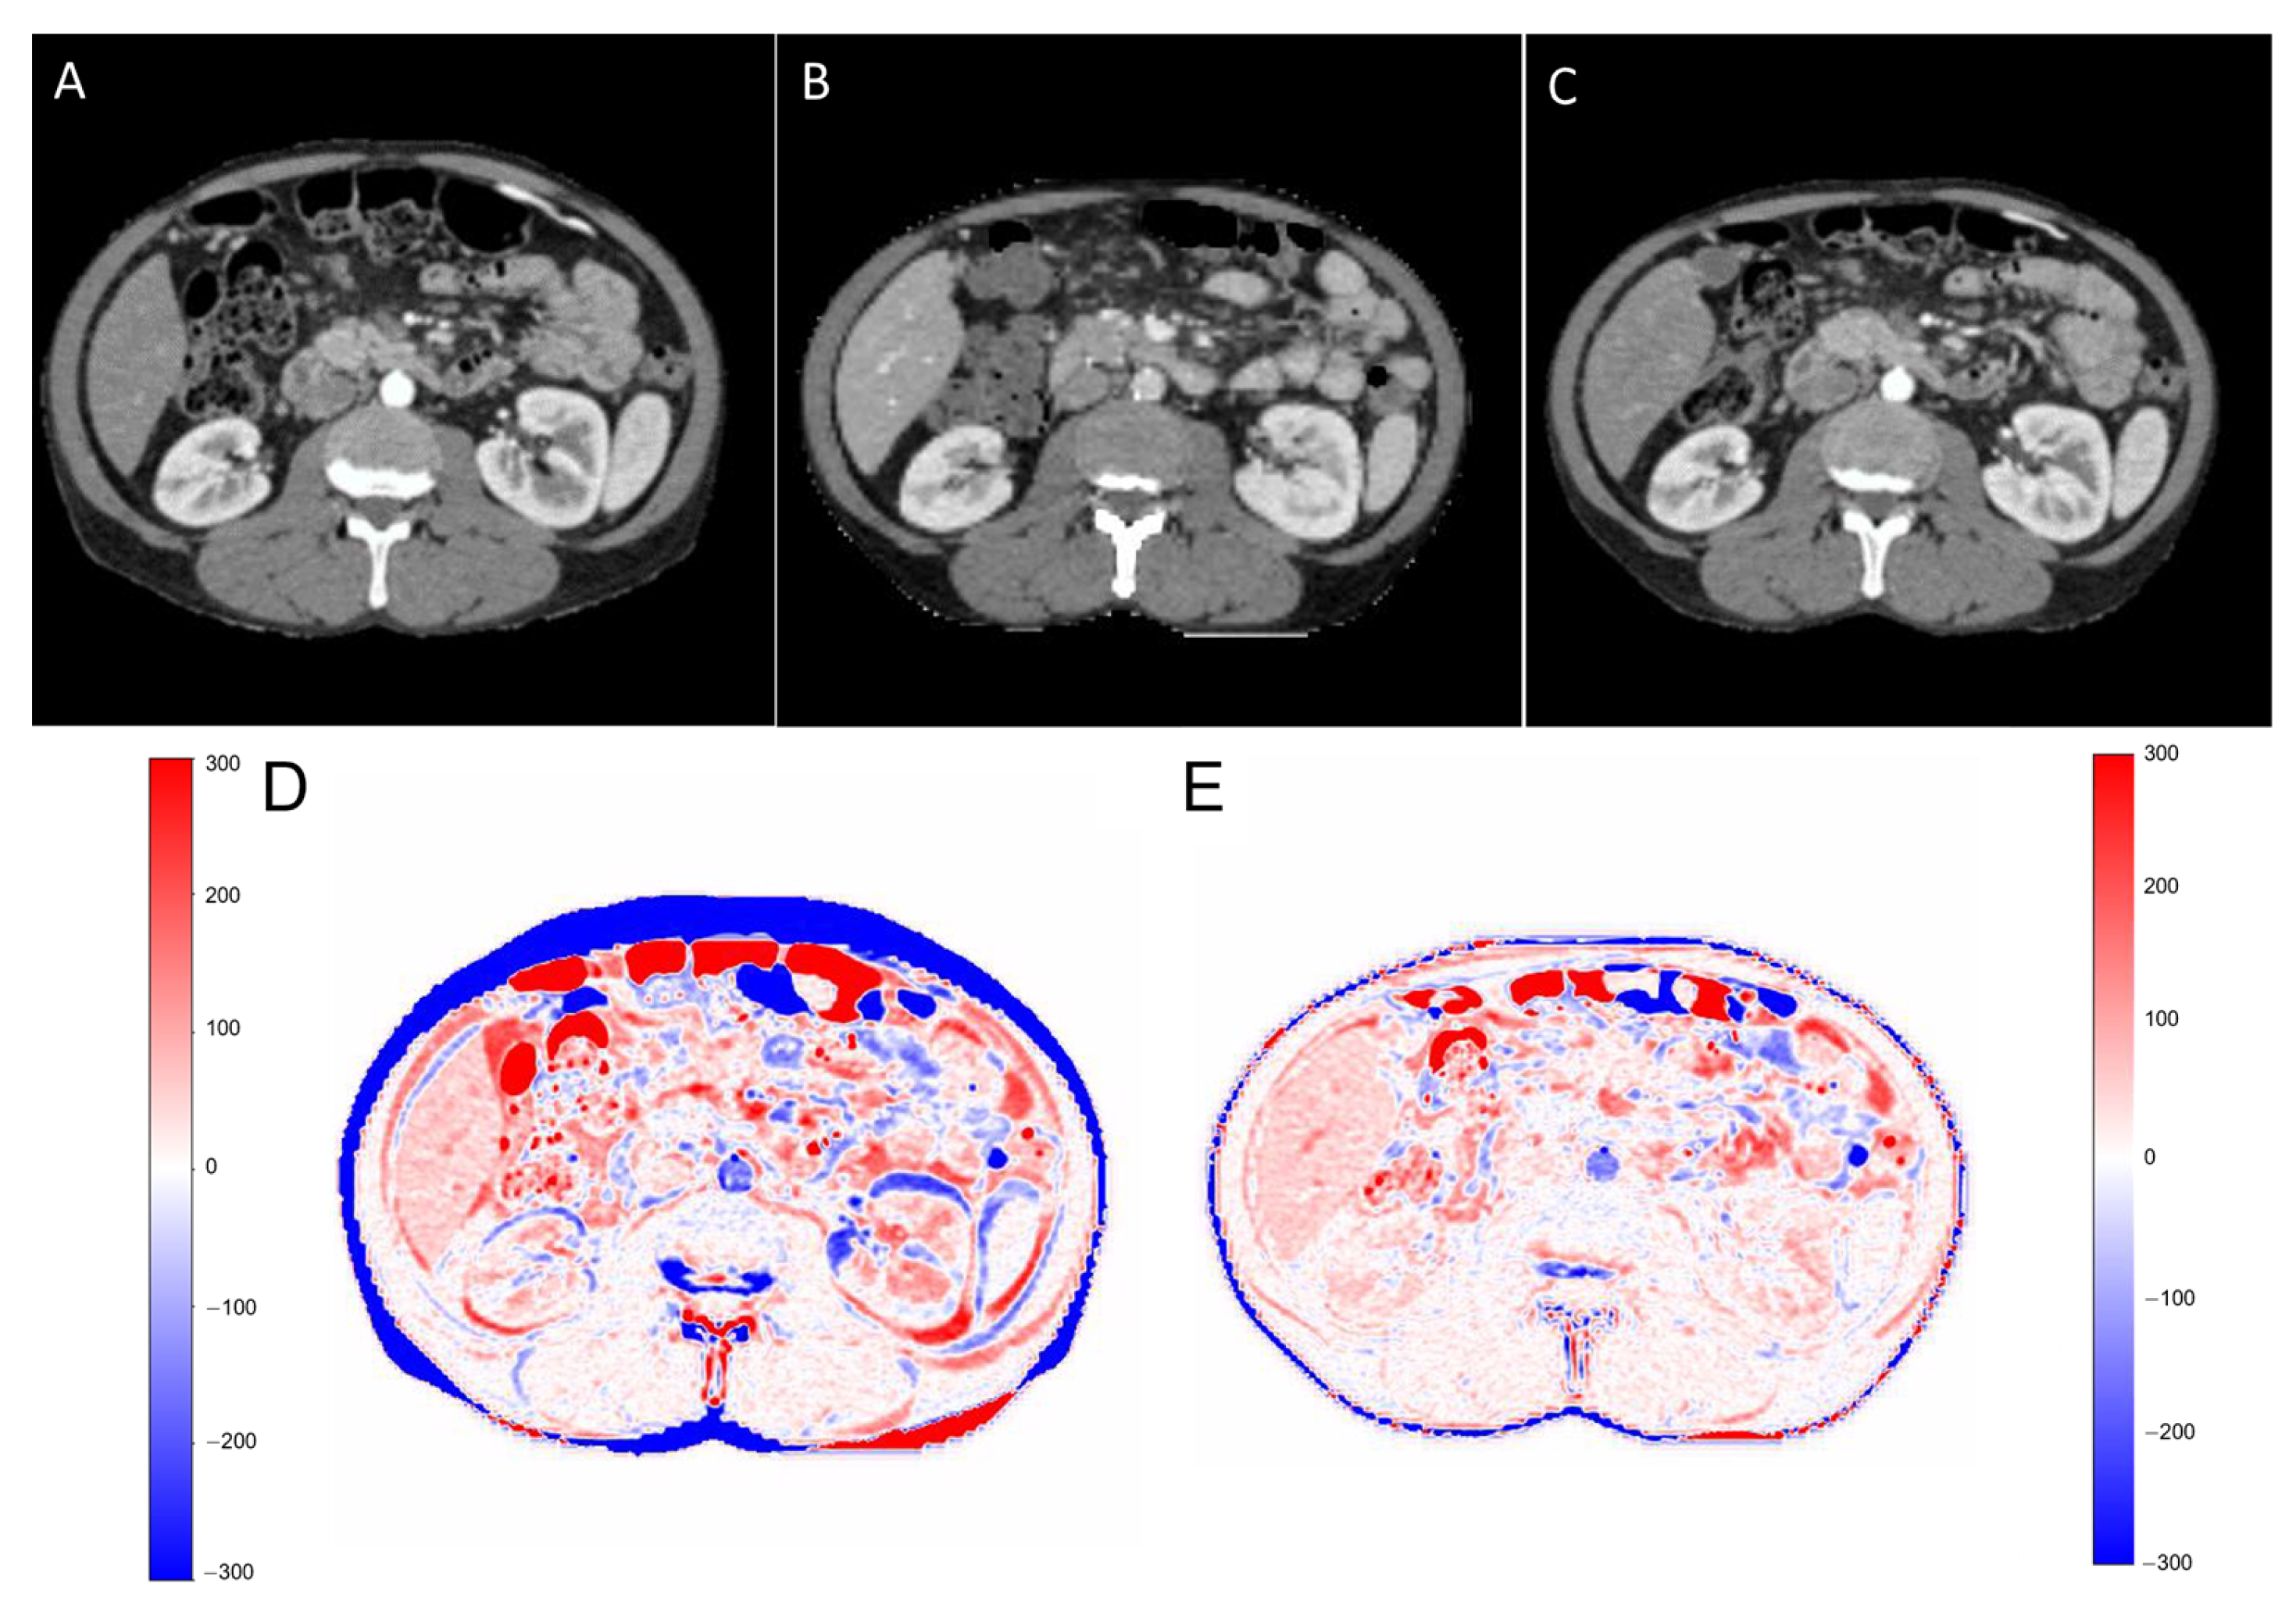

2.2. Deep Learning Model

2.3. Training and Testing of the Model

3. Results